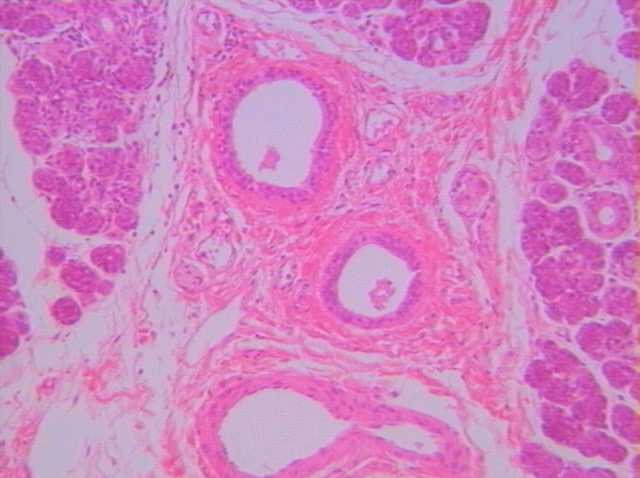

切片位置:唾腺(salivary gland)

切片倍率:100x

染色方式:h&e stain

低倍下(100x)觀察之唾腺組織,其腺體為結締組織分隔稱為小葉。唾腺之分泌物經由小葉內導管輸送匯集至結締組織間之小葉間導管,其導管之上皮組織為複層立方上皮。